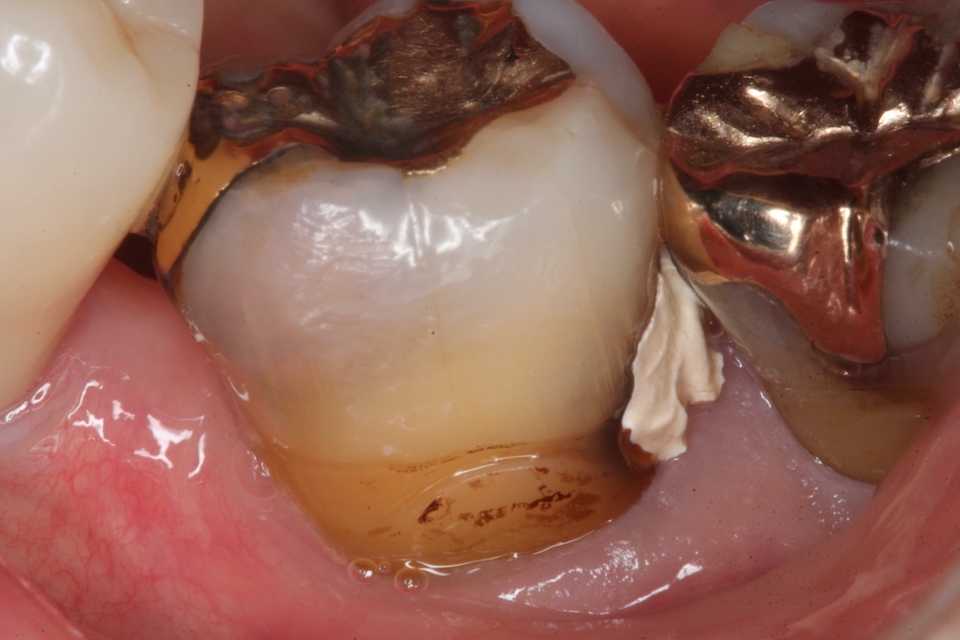

これが処置前の画像。亜鉛華ユージノールセメント貼付などの処置はしないで欲しいというのが本音。

セメントを削り取る時に露髄させたり、すでに露髄していて細菌を根管内に押し込んだりと増悪リスクが高いだけだ。前医はどうせ神経を取ってクラウンとか治療困難に付き抜歯してインプラントとか思っているので、セメントを剥がすことがあるなどとは最初から考えていないのだろう。

セメントと軟化象牙質(虫歯)を除去するときに痛みがなかったのですでに歯髄は失活(死んでいる)している可能性は高いが、

3MIX+α-TCPセメントで覆罩して

CR充填することにして、経過観察することにした。

髄腔に感染している時は腫れる等の症状が出るので、その時の対応になる。そのまま歯髄がミイラ化して(乾酪壊死)症状が出ないこともある。それはそれでOKだ。